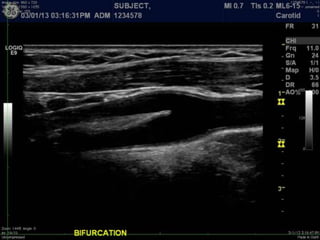

B-mode, 2D imaging

A Primer ofDiagnostic Ultrasonic Imaging Modalities B-mode, 2D imaging